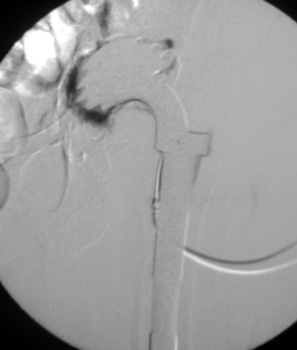

Dry tap secondary to sinus tract decompression

Sinus tract draining posteriorly